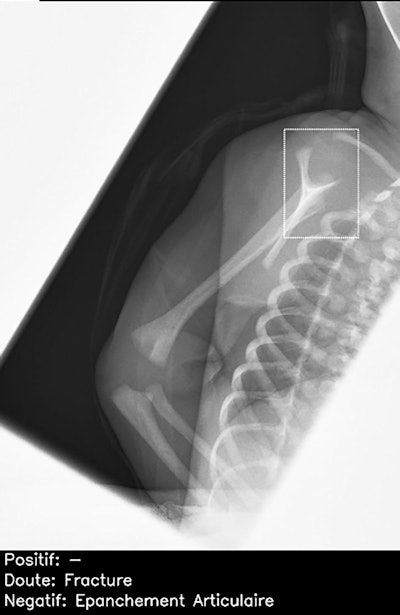

The AI candidate was Smarturgences v1.17.0, developed by French AI company Milvue and marketed since February 2020. It is used clinically in over 10 European hospitals and has been trained to assess MSK radiographs for fractures, swollen and dislocated joints, collapsed lungs, etc.

"We hope to retest the new AI model again in the future and see whether it can improve in test scores and pass more mock examinations!" said Shelmerdine, who is principal investigator of Fracture Study, the National Institute for Health and Care Research-funded U.K. project looking at how AI can be used to interpret pediatric imaging.

"We are developing AI algorithms to determine how we can better assess pediatric fractures on radiographs and also the impact this has on human decision-making in clinical practice," she said.